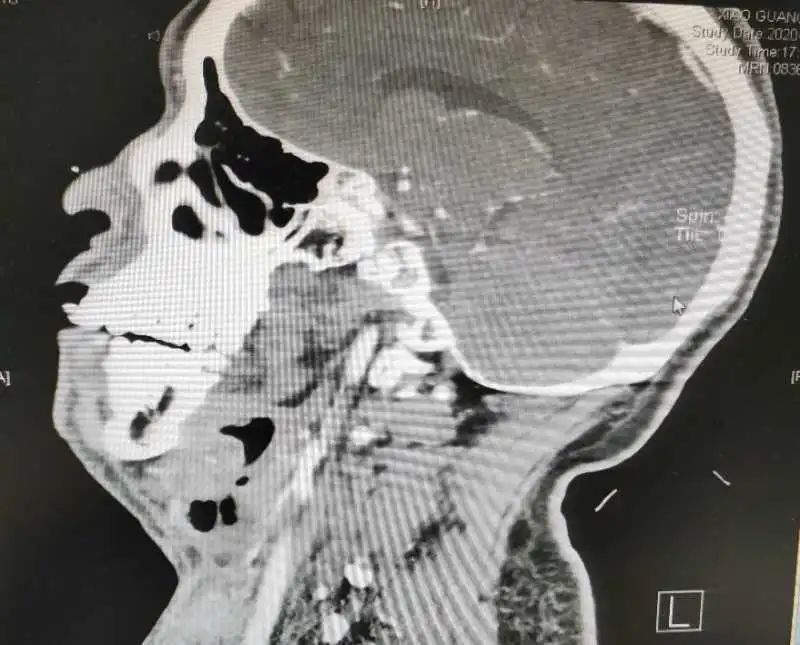

经过进一步检查显示,肖先生左侧扁桃体、左侧口咽旁、颌下、颈部、耳前、胸前壁软组织感染、脓肿形成,呈多间隙脓肿,散在大量积气,纵膈、肺部感染,脓肿尚未形成。耳鼻咽喉科医生朱先柏决定联合口腔科医师急诊下行双侧颌下、颈胸部脓肿切开探查引流术+气管切开术。

在手术后次日,肖先生口咽部、颌下区、颈胸部疼痛进一步好转,换药时引流管可冲出少量脓液。但术后第三日,患者自觉右侧颈部疼痛再次加剧,复查头颈面胸部CT回示:左侧脓肿及积气大部分吸收,肺部、纵膈感染已控制,但右侧颈部再次出现脓肿,且向深面进展。耳鼻咽喉科邓安春主任和朱先柏医师查看患者影像学检查后判断,应及时再次手术,以制止脓肿向颈动脉鞘及纵膈发展,于是当日再次急诊下行了右侧颈部脓肿切开探查引流术。